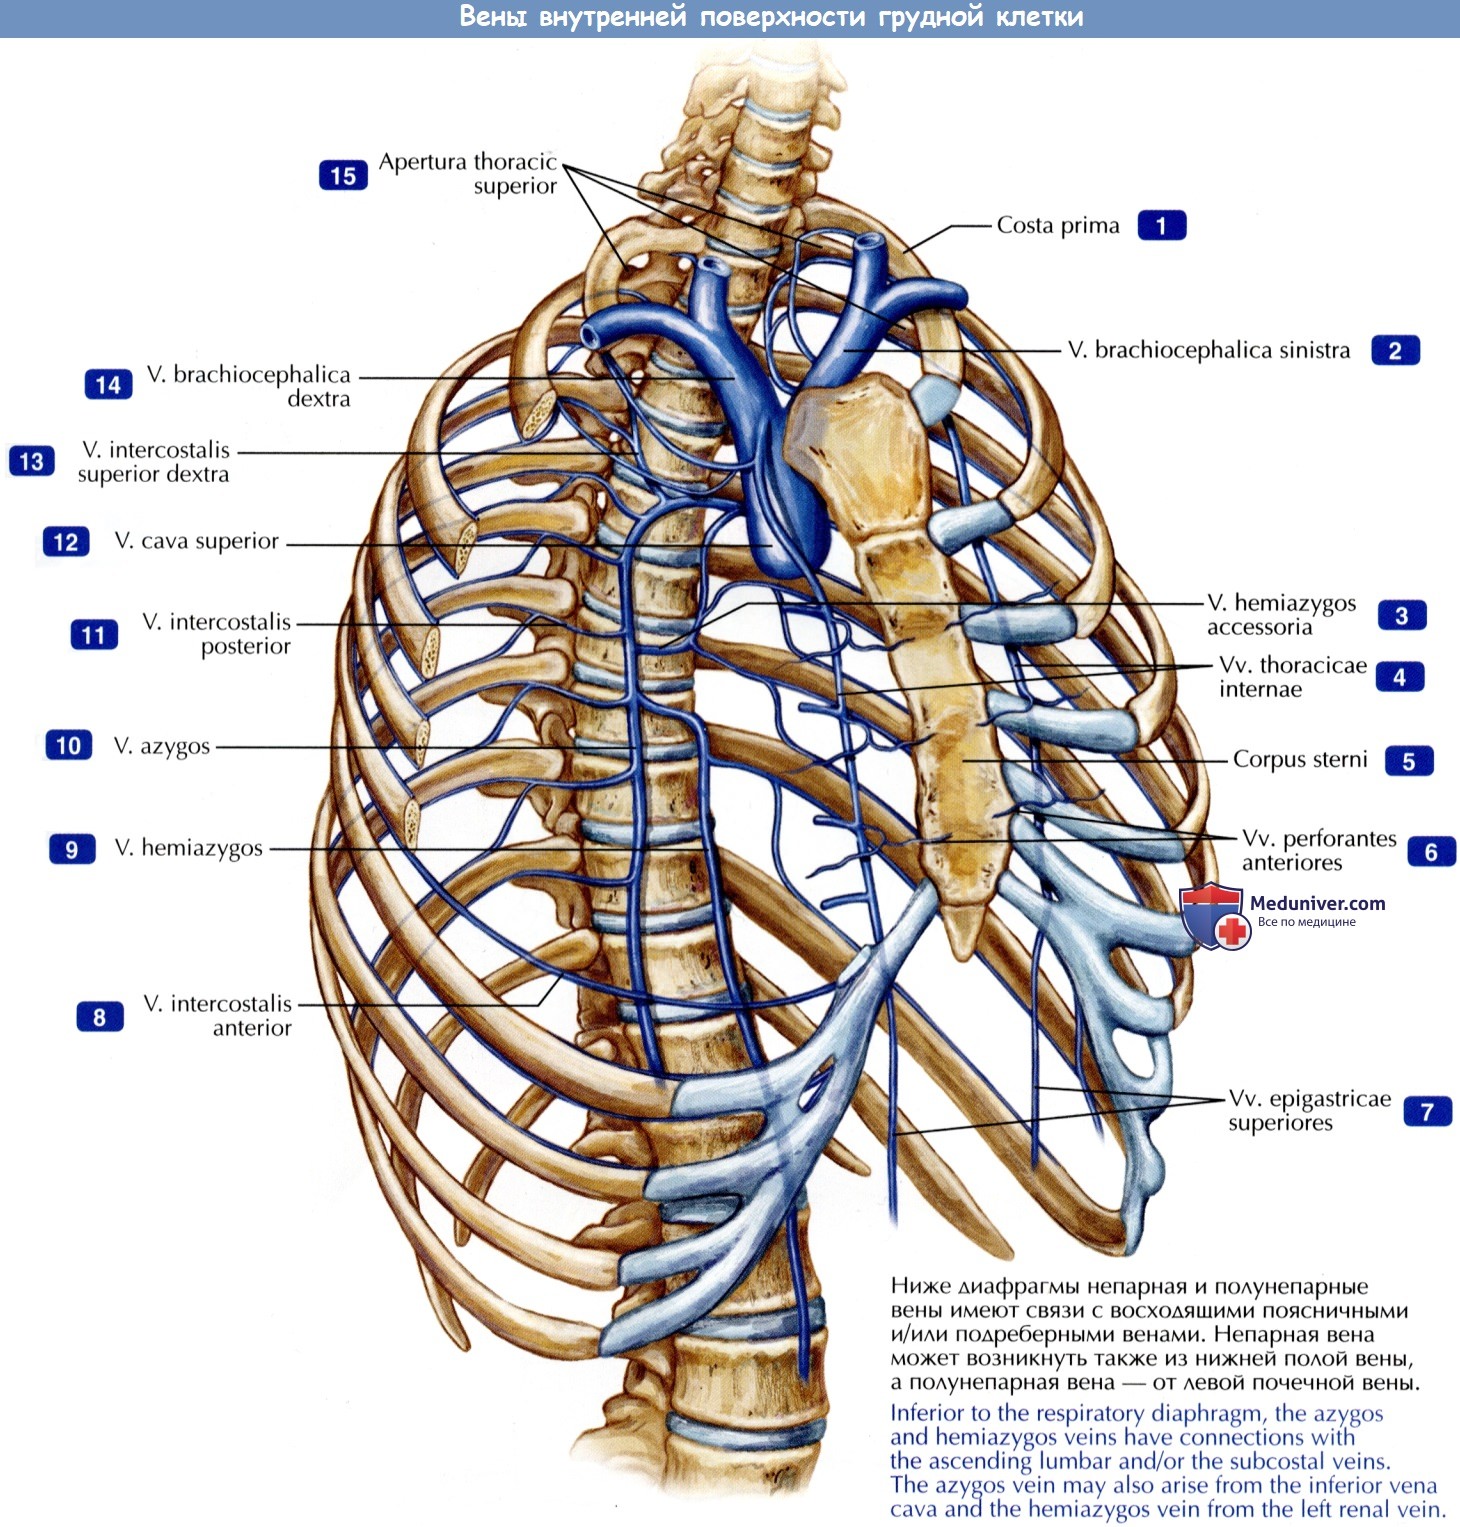

Анатомия Сердца: Расположение и Функции